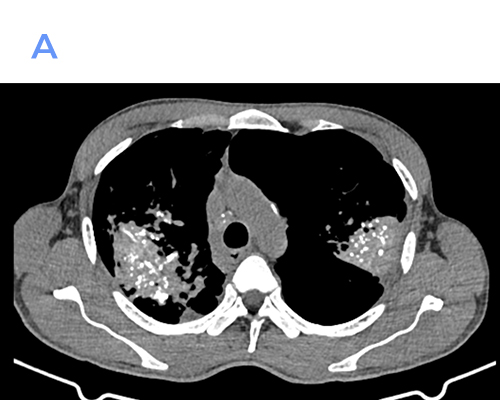

A midline defect in the frontal bone is likely through an unobliterated fonticulus frontalis with herniation of anterior frontal lobes through it with surrounding CSF.

NASO-FRONTAL ENCEPHALOCELE